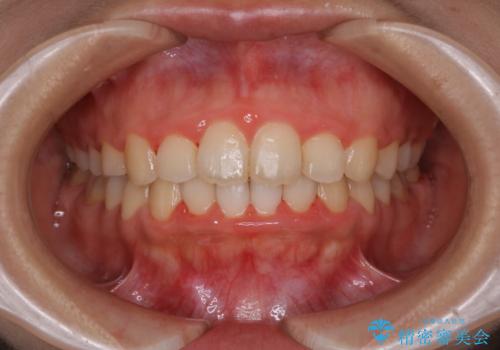

- 4年ほど前から地元の歯科医院にてインビザライン治療を行っていたが、引っ越し後に通いづらくなってしまったため、治療が途中で止まってしまっているとの事で来院されました。性格的にインビザラインの継続した使用が難しいとのことで、ワイヤー装置にて最終仕上げを行いました。

インビザラインは20時間以上の装着を厳守して頂くことで治療効果が期待できる治療となります。固定式のワイヤー装置に切り替えることで短期間で歯並びを整えることができ、大変喜んでいただけました。